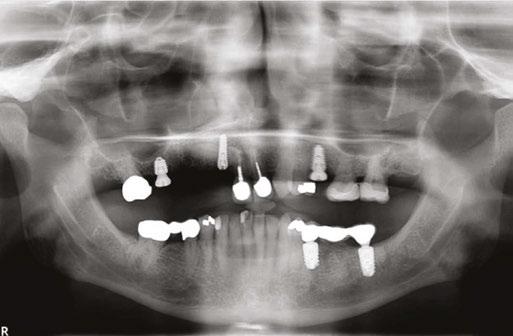

This is the presentation of the restoration of a 78-year-old male with multiple complicating factors.

Mr. Z has a skeletal Class III malocclusion. He has never received orthodontic treatment. The CBCT shows tooth No. 6 is present but horizontally impacted (Figure 4).

Based on age of patient, health history, and presence of the impacted canine, the patient was sent to an oral surgeon for evaluation. The initial consultation asked the surgeon to consider removal of impacted tooth No. 6 and placement of bone graft as a prelude to restoring site 2-7 with an implant-supported fixed bridge (Figures

Close inspection of the CBCT shows tooth No. 6 is ankylosed. The oral surgeon indicated extraction of tooth No. 6 would require block resection of bone with the tooth. The resulting defect would have required extensive bone grafting

added time and cost to this case.

On the day of surgery, the patient had MegaGen AnyRidge® implants placed at the following sites under local anesthesia:

• Tooth No. 7: trans-canine placement of 4.0 mm x 13 mm

• Tooth No. 3: 5.0 mm x 7.0 mm with small crestal approach sinus graft

• Tooth No. 13: 4.0 mm x 10.0 mm implant

Retaining tooth No. 6 and placing the dental implant through the impacted and ankylosed tooth provided a new set of challenges. Keeping the ankylosed canine in place reduced the need for additional surgery; however, with the retention of the canine, insufficient interarch space would be available for a zirconia or resin-composite restoration. Because the interarch space was limited, a porcelainfused-to-metal restoration was used to complete the case.

Figures 7 and 8: Healing abutments in place Figure 4: Pretreatment panoramic x-ray. Note position of maxillary right canine Figures 5 and 6: Pretreatment CBCT scan with treatment planning software. Virtual implant placement at site 10 shows thin buccal bone. Buccal bone graft was provided at time of surgery Figures 9 and 10: Porcelain-on-metal framework ready for delivery

In the 1970s and early 1980s, the surgery was extensive, painful, and the failure of these modalities was catastrophic for the patient. Photos like Figures 13A and 13B remind us how far the science and technology of implant treatment has come in a brief period. The best we can do for our patients is to put their interests first, offer clear choices, and provide evidence-based dental treatment (Figure 14).

2. Paton G, Fuss J, Goss AN. The transmandibular implant: a 5- and 15-year single-center study. J Oral Maxillofac Figure 14. Post implant placement. This CBCT shows implant at site 10 through the impacted canine. Implant at site 3 was placed right against the sinus floor Figures 13A and 13B: 13A. Trans-mandibular dental implants. 13B. Subperiosteal implants Figure 11: Surgical site on day of surgery Figure 12: Implant placement of tooth No. 7 with buccal bone graft